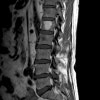

MRI : Low signal in T1, High signal in T2

MRI : 유골골종(Osteoid osteoma) & 골아세포종(Osteoblastoma)

진단 : MRI with GD

MRI : Flare reaction in T2